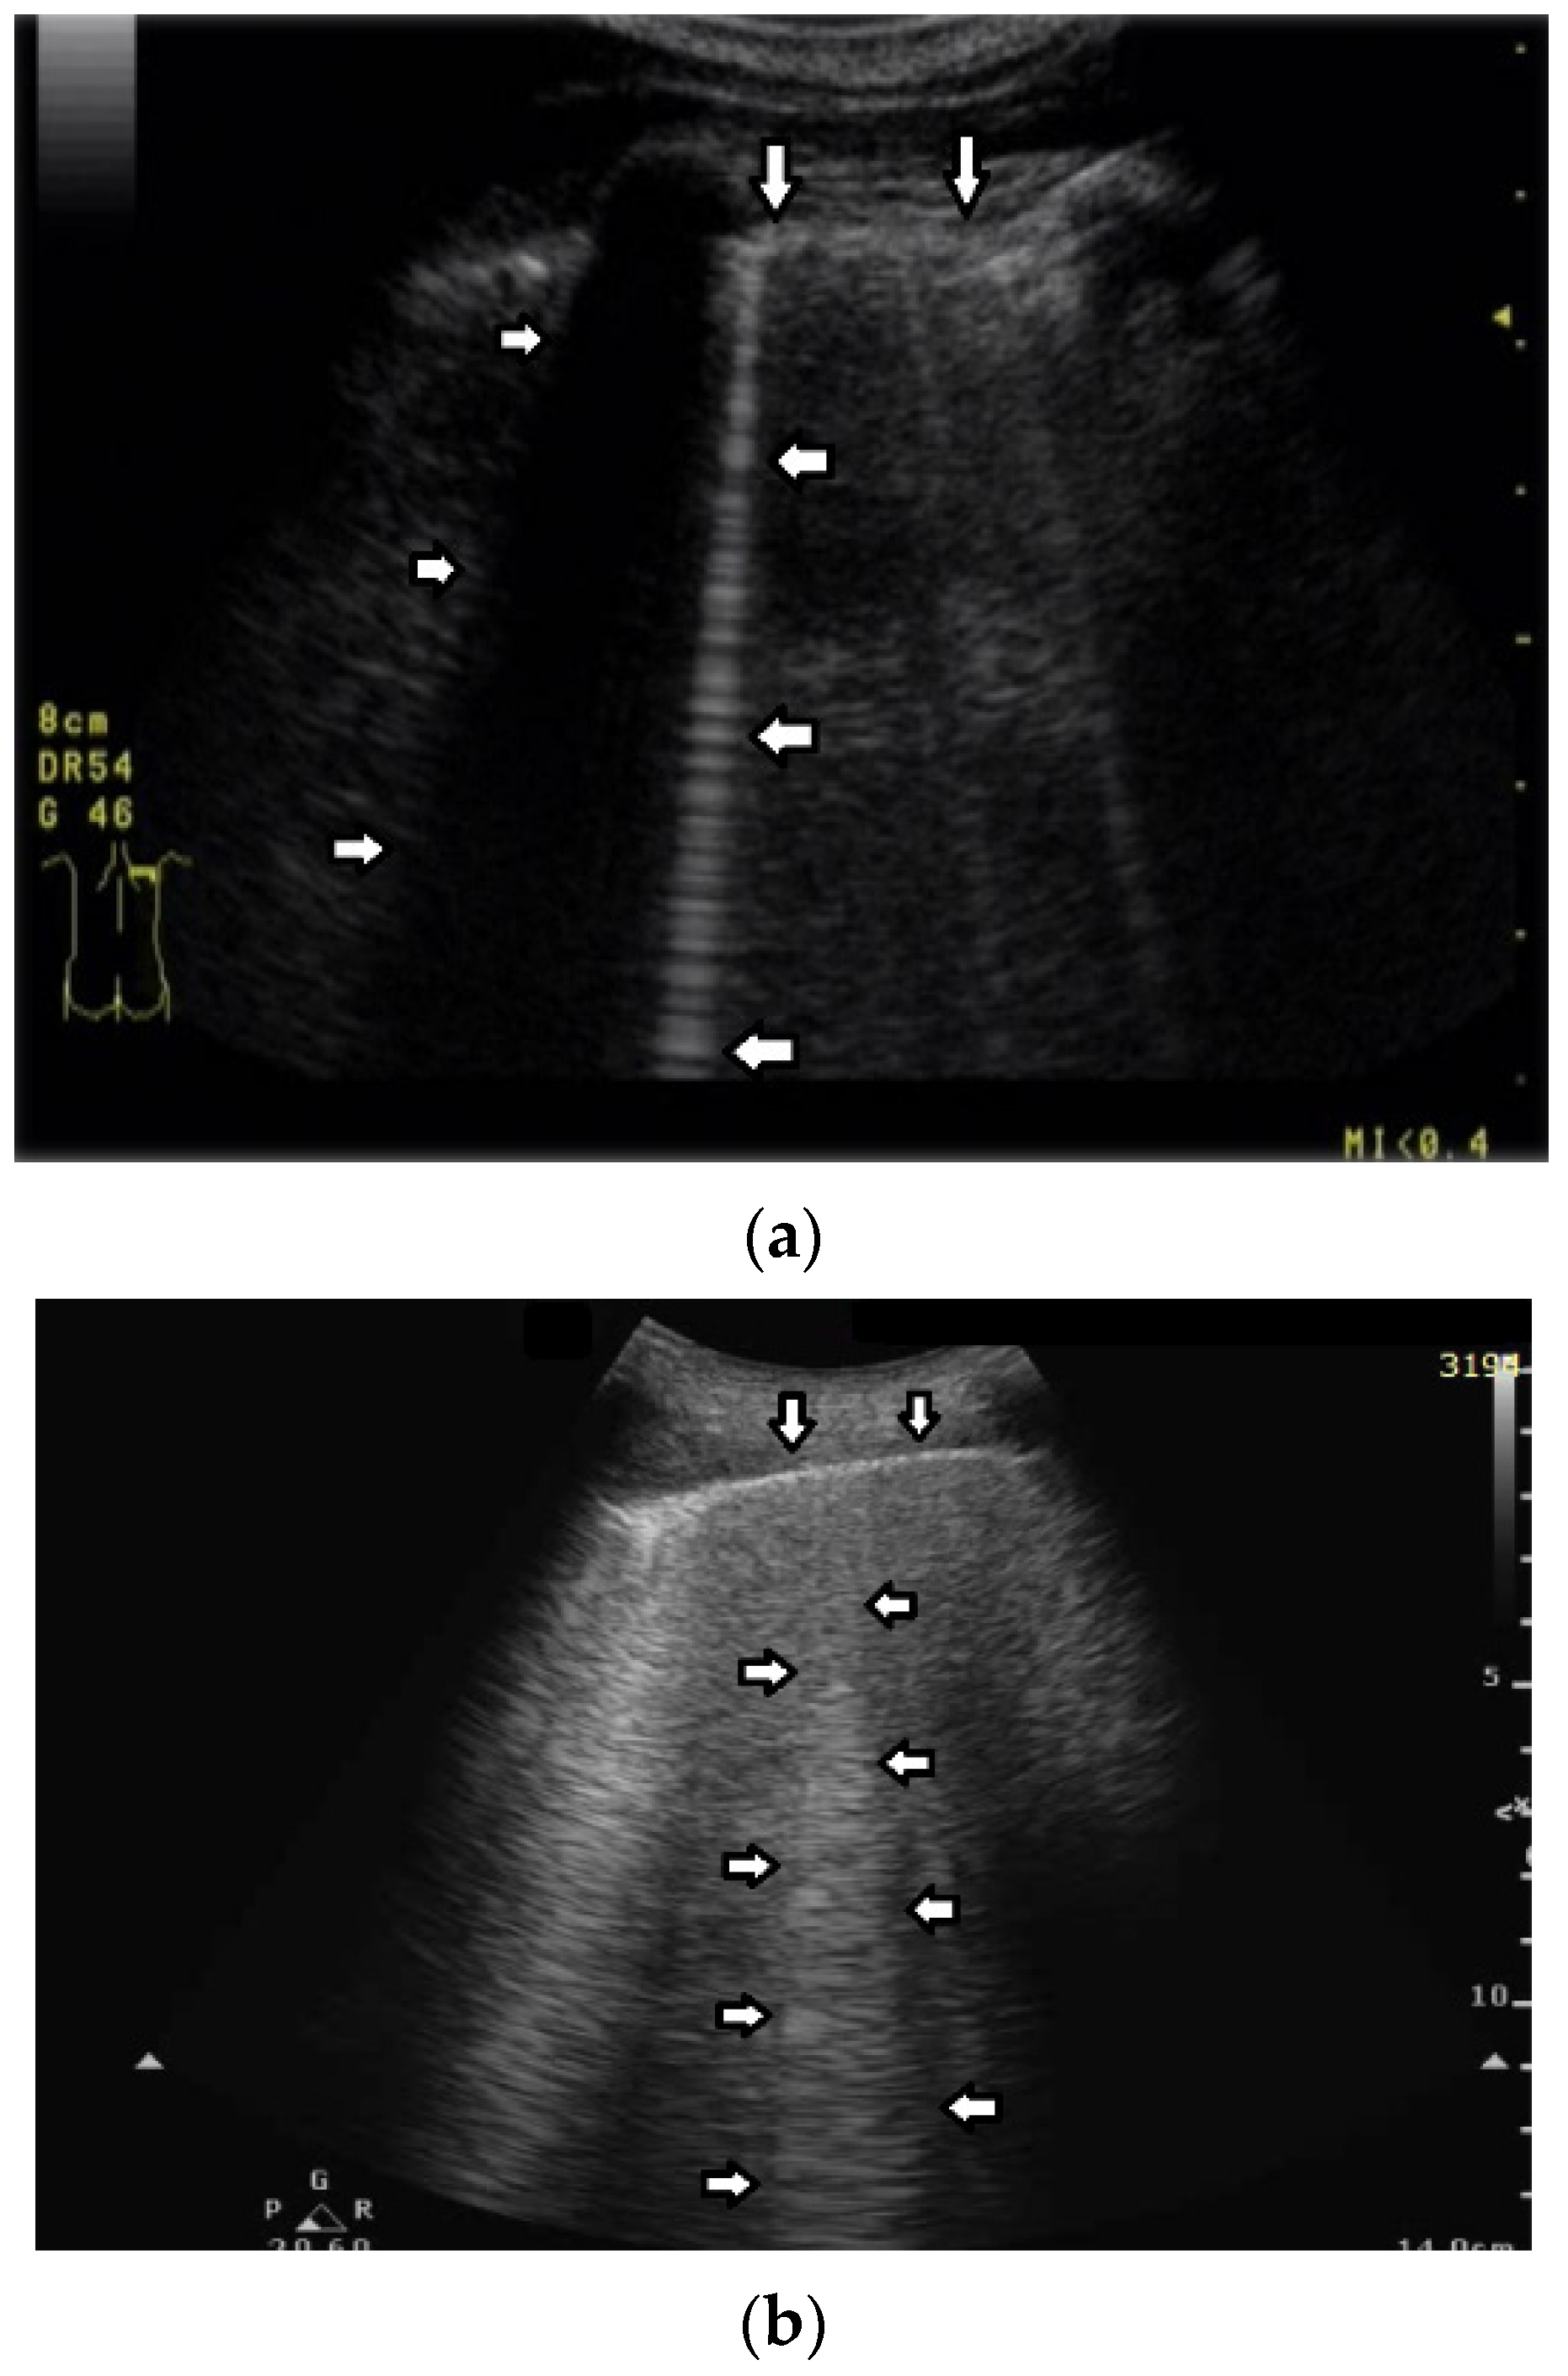

- Question 8:

Based on clinical observations, we know that in pulmonary fibrosis, B lines often reduce their length when higher frequencies are used on a convex probe (from 2 MHz up to 6 MHz) (see Figure 4a,b). In the case of cardiac edema, the length of a B line is often stable, irrespective of the frequency modification (see Figure 4c,d) [3]. Why does the length of B lines sometimes change when varying the pulse central frequency, whereas sometimes the length does not significantly change?

Figure 4.

(a) Pulmonary fibrosis in the course of interstitial lung disease: down arrows—pleural line; left arrows—B line artifact observed at 2 MHz frequency. (b) Pulmonary fibrosis in the course of interstitial lung disease: down arrows—pleural line; left arrows—vertical artifacts observed at 6 MHz frequency. The image was obtained from the same patient and identical assessment site as in Figure 4a. (c) Cardiac edema: down arrows—pleural line; left arrows—B-line artifacts observed at 2 MHz frequency. (d) Cardiac edema: down arrows—pleural line; left arrows—B-line artifacts observed at 6 MHz frequency. The image was obtained from the same patient and identical assessment site as in Figure 4c.

- Answer 8:

Look at the entire image, and you will find the answer. When using the 2 MHz frequency, the image (Figure 4a) is brighter everywhere: the thoracic wall is brighter; the pleura line is brighter; the two lateral sides of the image (where there are no artifacts) are brighter, and the artifacts themselves are brighter. In my opinion, the problem is primarily given by the attenuation, which increases when increasing the frequency. In order to compensate such an effect, you should change the TGC. As a rule of thumb, you can consider an attenuation coefficient of 1 db/cm/Mhz. When varying the frequency from 2 MHz to 6 MHz, you are introducing an additional attenuation of 4db per centimeter. From a practical point of view, when using the 6 MHz frequency, the probe receives a signal from the depth of half a centimeter, whose amplitude is less than half the amplitude of the signal it would receive from the same depth if a 2 MHz pulse were used. Moreover, it is worth noting that the ratio between the amplitudes of the two temporal signals s6(t) and s2(t) (the echoes received by the probe) decreases exponentially when the delay t increases.

The answer is a bit more complex when cardiac edema is considered. In the case of fibrosis, larger acoustic traps and wider linking channels are, in general, expected that reradiate almost the entire power spectrum of the trapped acoustic pulse. In this case, attenuation is probably the main factor that influences the artifact length when varying the frequency. Therefore, the artifact length decreases when increasing the pulse central frequency since attenuation increases when increasing the frequency. On the contrary, in the case of cardiac edema, smaller acoustic traps and narrower linking channels are expected at the early stages of the pathology. Smaller traps can reradiate only a few harmonics, and the overlapping between the pulse spectrum and the spectral signature of the trap affects the artifact length much more than the attenuation factor. In these cases, the trap response to pulses with different frequencies is unpredictable.